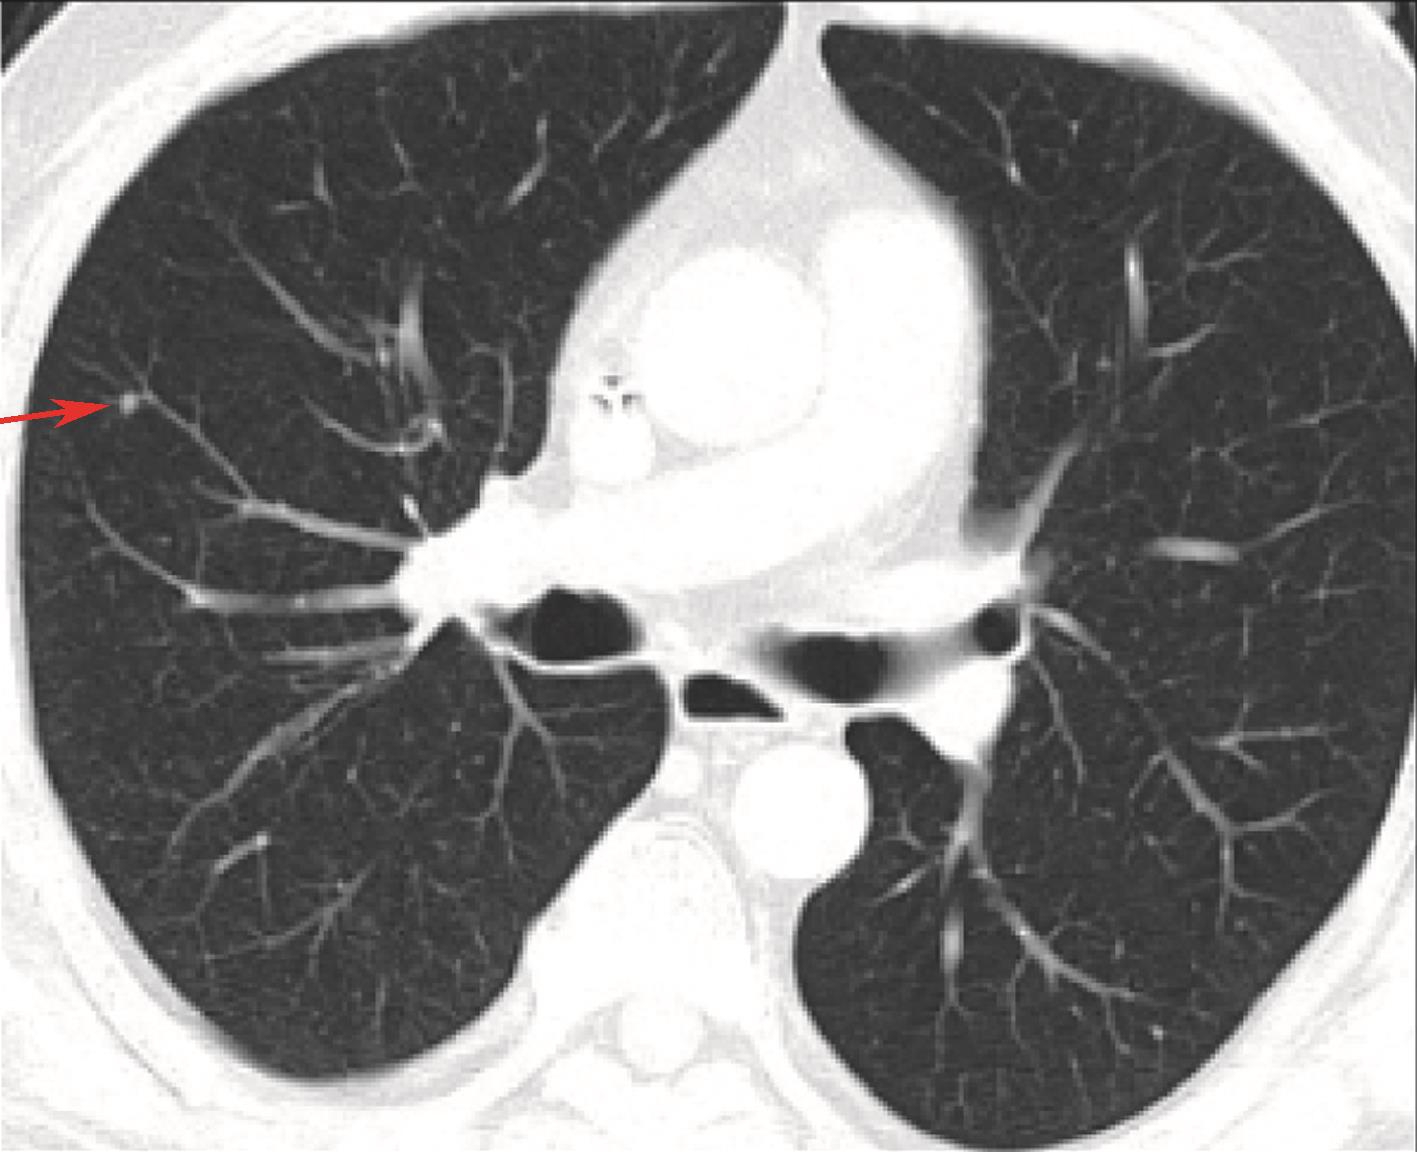

2016-03-17起进入西妥昔单抗维持治疗,2016-06右肺出现新发可疑小结节(图6),不除外PD,予停用西妥昔单抗,与患者及家属沟通后,定期复查。

图6 2016-06胸腹盆增强CT,右肺新发小结节

2016-09 CT示右肺小结节缩小、密度减低,2016-12、2017-03、2017-07复查胸腹盆CT及颈部MRI无明显变化。